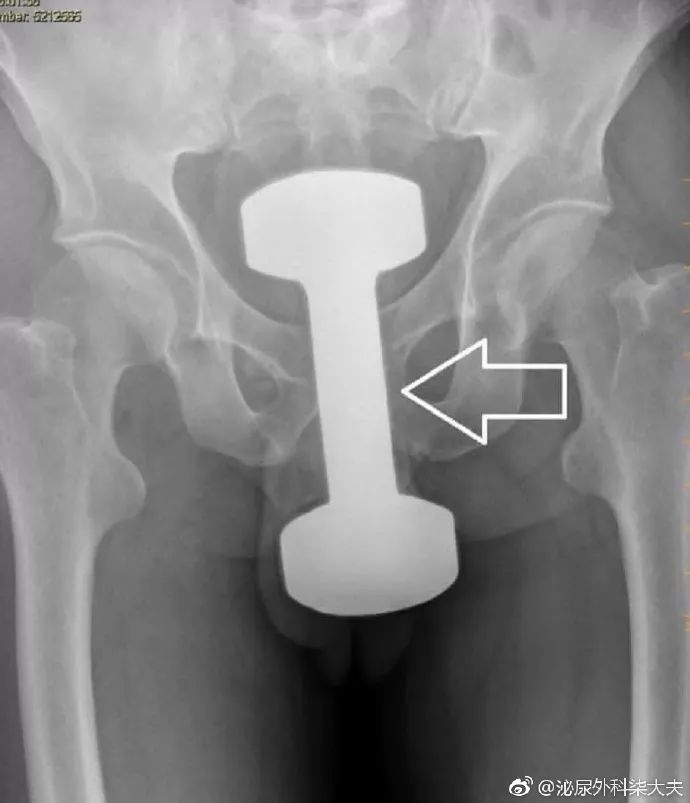

春节假临近结束,一位50多岁的男子发现了这种新奇玩法。

把哑铃塞进了肛门,到急诊后隐瞒了部分病史,直到拍片子的时候医生才发现了这个重达10斤的哑铃的“重大秘密”。

最后这个哑铃在足够的润滑和牵引后被从直肠中取出。